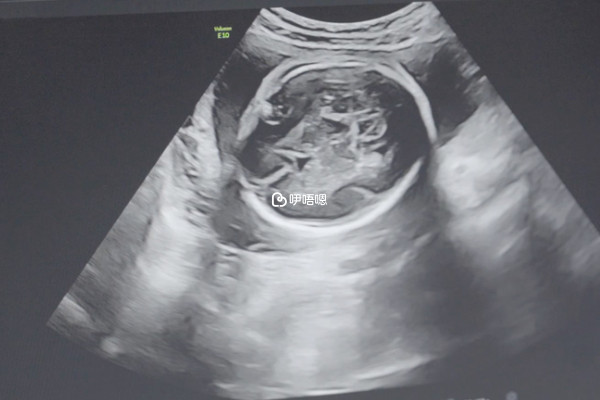

- 4. 梅毒患者還可以通過輔助生殖技術實現生育,但是要先將體內的病毒滴度減值能夠生育的範圍,這樣才不會傳染給胎兒。

梅毒患者治癒後和正常人都是差不多的,所以患者也不必太擔心,只要是在懷孕前將滴度保持在1:2時就不影響正常懷孕。這種病的複發率很高,所以說女性在治療後也應該按時進行復查,才能避免引起他人感染。